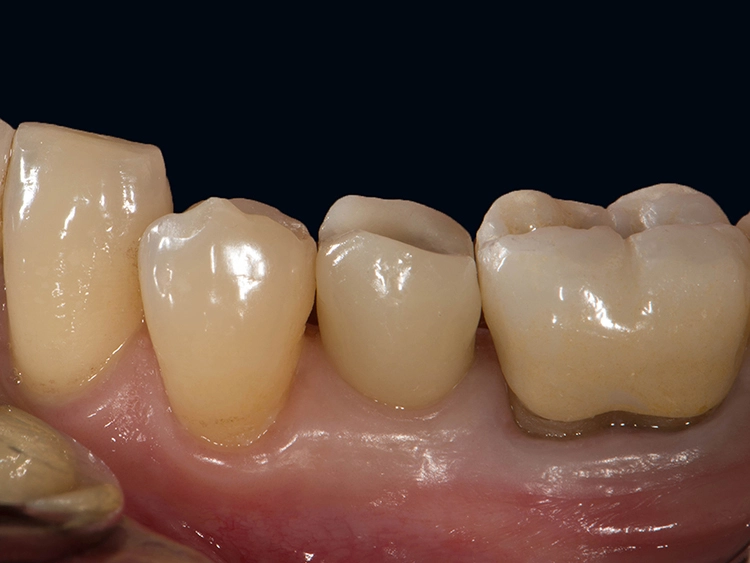

Zweiteilige Implantatsysteme würden darüber hinaus mit einer höheren prothetischen Flexibilität punkten, weil die Aufbauten individueller gestaltet werden können. Dr. Röhling: „Das kann ein Vorteil sein, wenn etwa die prothetische Achse korrigiert werden muss.“ Hinzu kommt, dass bei Anwendung von zweiteiligen Systemen eine Zementierung, die für Fehlerquelle anfällig gesehen wird, entfällt, da sie eine reversibel verschraubte Befestigung erlauben, während bei einteiligen Implantaten die Suprakonstruktion nur zementiert gestaltet werden kann (siehe Fallbeispiel, Abbildungen 1 bis 10).